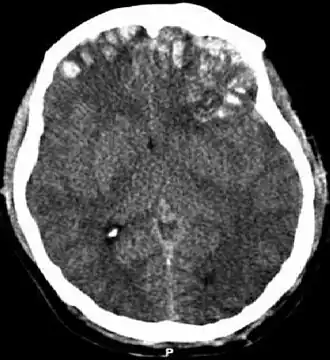

Le scanner cérébral permet de voir l'étendue des lésions : présence d'une fracture, taille et localisation d'un hématome, conséquences sur les ventricules cérébraux, présence ou non d'un œdème cérébral. Une admission en unité de réanimation ou en soins intensifs de neurochirurgie est nécessaire. L'utilisation systématique d'une perfusion hypertonique dans le but de limiter l'œdème cérébrale a une efficacité discutée[22], de même qu'une ventilation hyperoxique (avec plus d'oxygène que de besoin)[23]. Toutefois, la mise sous ventilation artificielle est très souvent nécessaire. L'intérêt de la mise sous hypothermie est également incertain[23].

L'un des éléments du traitement est le contrôle d'une hypertension intracrânienne secondaire à l'œdème cérébral et/ou à l'obstruction des voies de circulation du liquide cérébrospinal. Les corticoïdes s'avèrent décevants dans ce cas[24]. L'évacuation chirurgicale d'un hématome intracérébral permet une décompression. La pratique d'une ouverture crânienne, en dehors de tout hématome, permet également de faire baisser la pression intracrânienne[23].

La surveillance repose, suivant les cas, sur l'évaluation de l'état de conscience, la mesure de la pression intracrânienne, l'imagerie, l'électroencéphalogramme. En cas d'évolution neurologique péjorative aboutissant à un diagnostic de mort cérébrale et suivant l'état général du patient, une discussion sur un éventuel don d'organe doit être faite en respectant les réglementations.